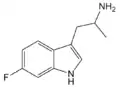

α-Alkyltryptamines are a group of substituted tryptamines which possess an alkyl group, such as a methyl or ethyl group, attached at the alpha carbon, and in most cases no substitution on the amine nitrogen.[17][18][19] α-Alkylation of tryptamine makes it much more metabolically stable and resistant to degradation by monoamine oxidase, resulting in increased potency and greatly lengthened half-life.[19] This is analogous to α-methylation of phenethylamine into amphetamine.[19]

Many α-alkyltryptamines are drugs, acting as monoamine releasing agents, non-selective serotonin receptor agonists, and/or monoamine oxidase inhibitors,[20][21][22][23] and produce psychostimulant, entactogen, and/or psychedelic effects.[17][18][19] The most well-known of these agents are α-methyltryptamine (αMT) and α-ethyltryptamine (αET), both of which were used clinically as antidepressants for a brief period of time in the past and are abused as recreational drugs.[18][19] In accordance with its action as a dual releasing agent of serotonin and dopamine, αET has been found to produce serotonergic neurotoxicity similarly to amphetamines like MDMA and PCA, and the same is also likely to hold true for other serotonin and dopamine-releasing α-alkyltryptamines such as αMT, 5-MeO-αMT, and various others.[24]

5-Fluoro-αMT | 1-(5-fluoro-1H-indol-3-yl)propan-2-amine | 712-08-3 |

5-Fluoro-αET | 1-(5-fluoro-1H-indol-3-yl)butan-2-amine | 1380137-98-3 |